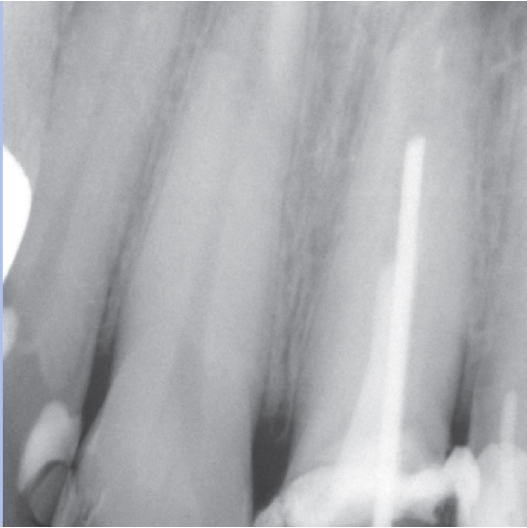

After

After Root Canal treatment